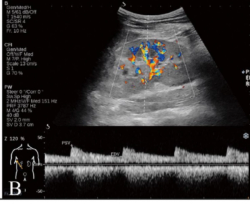

Known as the "Swiss Army knife" of healthcare, point-of-care ultrasound—or POCUS—has come a long way.

A low-cost, pain-free, user-friendly modality, POCUS can be used at the bedside, in the ED, ICU, OR, and in the field. It allows users to quickly diagnose a host of conditions, and it can help with procedural guidance. Its many benefits cannot be denied. No doubt, POCUS is a multi-faceted tool—the Swiss army knife of healthcare— that is in high demand.

POCUS is a smart investment for most hospitals as it is portable, and can be shared among departments if necessary—making it a practical and affordable modality. Moreover, POCUS is lightweight, easy-to-use, and can be utilized in a wide array of applications and practices, such as emergency medicine, critical care, anesthesiology and orthopedics/sports medicine.

It’s difficult to find another modality that can do so much for so many medical areas. Ultrasound has become an integral modality in emergency medicine in the U.S. in the last two decades and has established itself as the standard in the clinical evaluation of the emergency patient.

As a non-invasive technology, POCUS has proven to be a safe, cost-effective, and powerful tool for diagnosis and for the guidance of interventional procedures within many clinical environments.